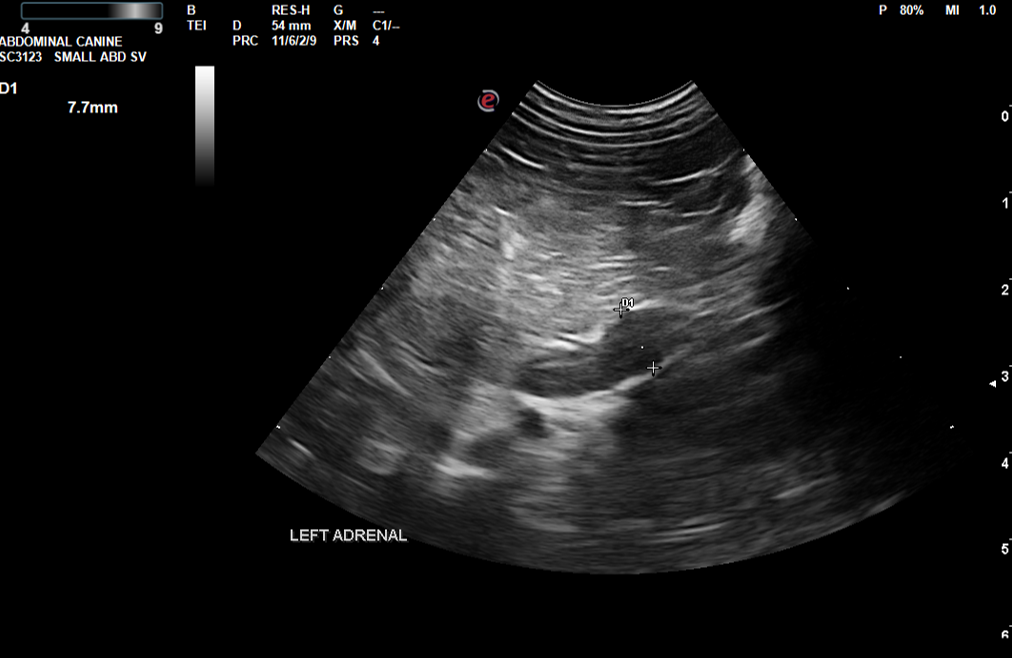

Image 1: Patient A - Left Adrenal

Image 3: Patient B - Left Adrenal